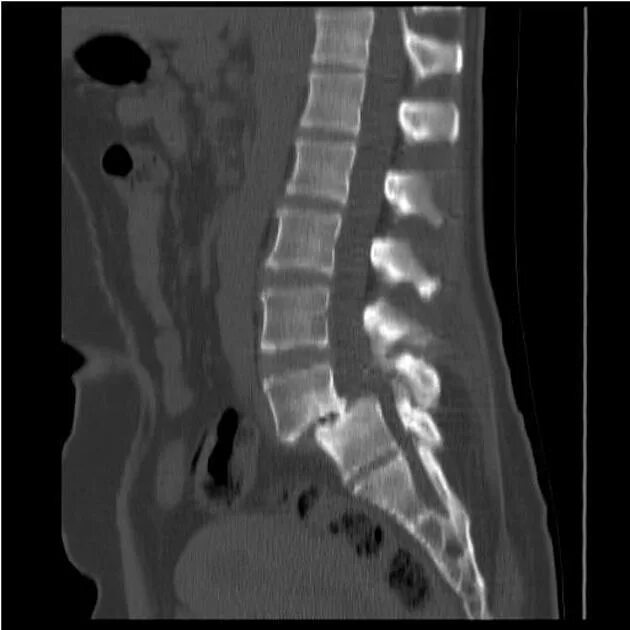

Смещение позвонков поясничного операция